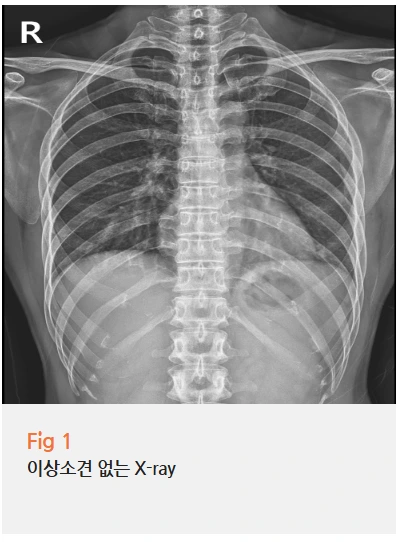

일단 X-ray부터 찍어봤어요.

다행히 골절은 아니었어요.

%EA%B7%B8%EB%A6%BC4.png?type=w966

"아, 다행이다. 그럼 근육통이네요?"

아니에요;;

골절이 아니라고 해서 단순 근육통인 건 아니거든요.

X-ray에는 안 보이고, CT를 찍어도 명확하지 않은 경우가 많거든요.